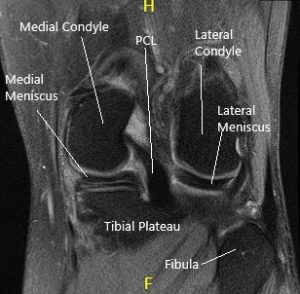

MRI of the left knee suggested tear of the posterior horn and posterior horn/body segment junction medial meniscus, with mild meniscal extrusion into the medial gutter and mild chondromalacia patella.

MRI of the knee in sagittal and coronal sections